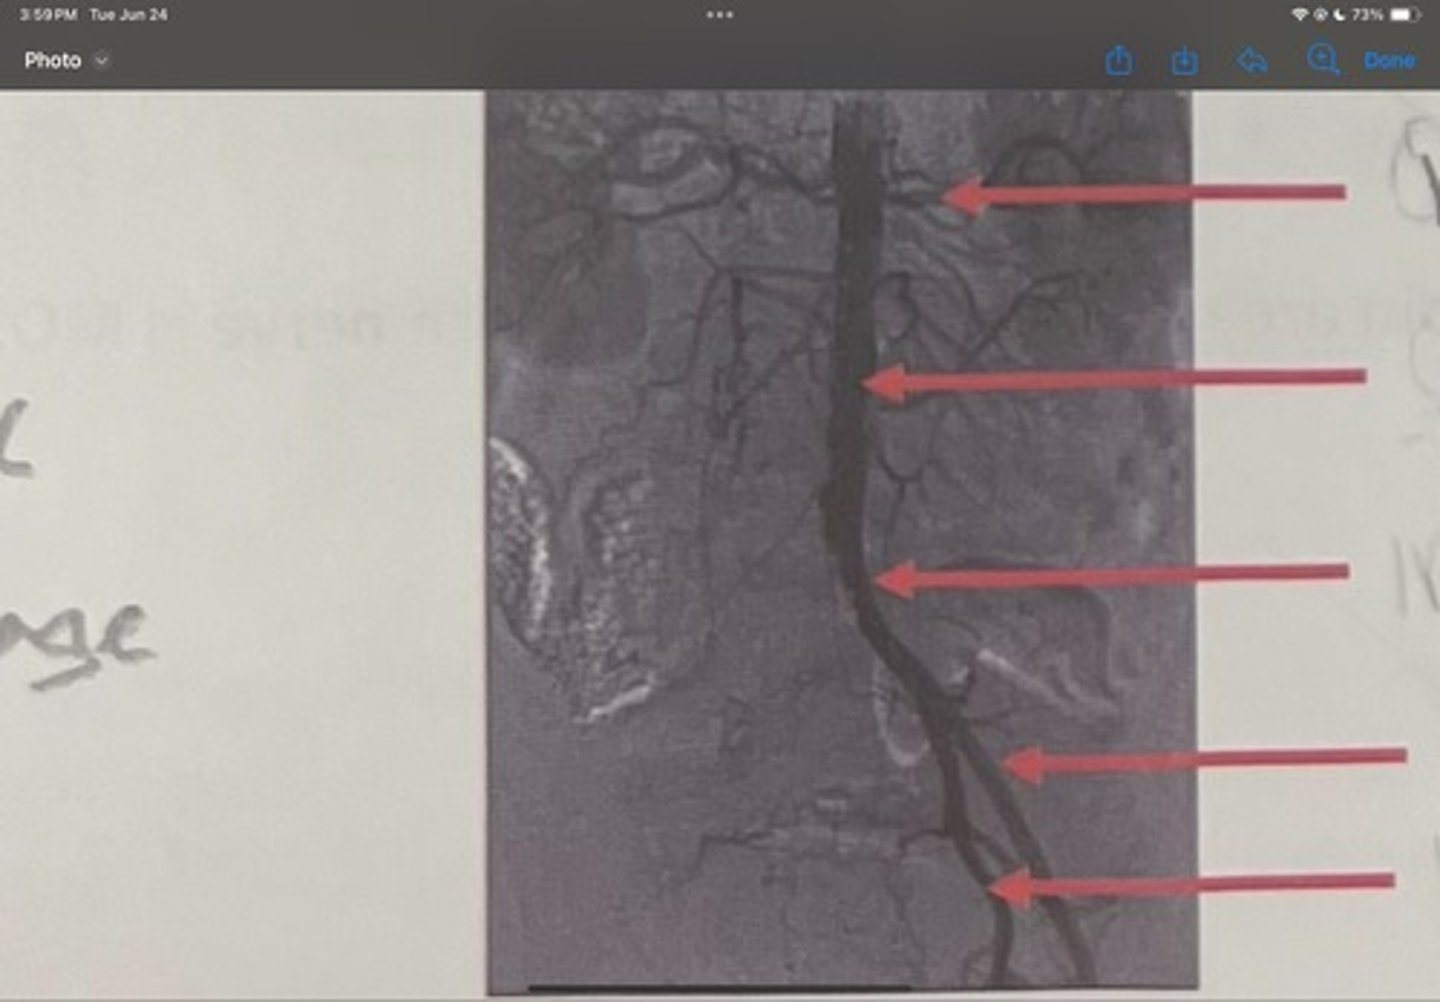

Renal artery

What is the 1st one

Abdominal aorta

What is the 2nd one

Common iliac artery

What is the 3rd one

External iliac artery

What is the 4th one

Internal iliac artery

What is the 5th one

right common iliac artery blockage

What is the pathology of the image